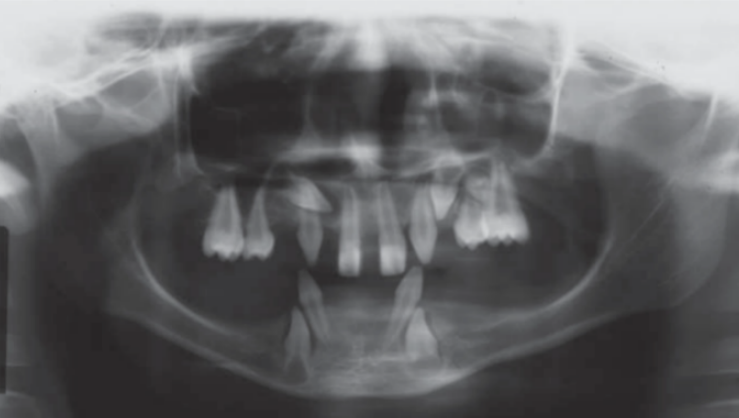

L’ edentulia può essere parziale o totale (Fig.1) e secondo Petersen ha dei fattori di rischio causali e dei fattori di rischio secondari. [1],[2]

I fattori di rischio causali sono: malattie genetiche come la displasia ectodermica (La Fig.2 mostra la rx panoramica di un ragazzo di 16 anni affetto da questa malattia), malattia parodontale, lesioni cariose, lesioni traumatiche e lesioni iatrogene. [3] I fattori di rischio secondari, cioè che influenzano l’insorgenza dell’edentulia sono: abitudini alimentari, abitudini d’igiene orale e la possibilità di accesso alle cure odontoiatriche. [4]

Figura 2 rx panoramica di un ragazzo di 16 anni affetto da Displasia ectodermica tratta da “Rojas, Lida Velazque, and Gisele Dalben da Silva. ‘Displasia Ectodérmica Hipohidrótica: Características Clínicas y Radiográficas”